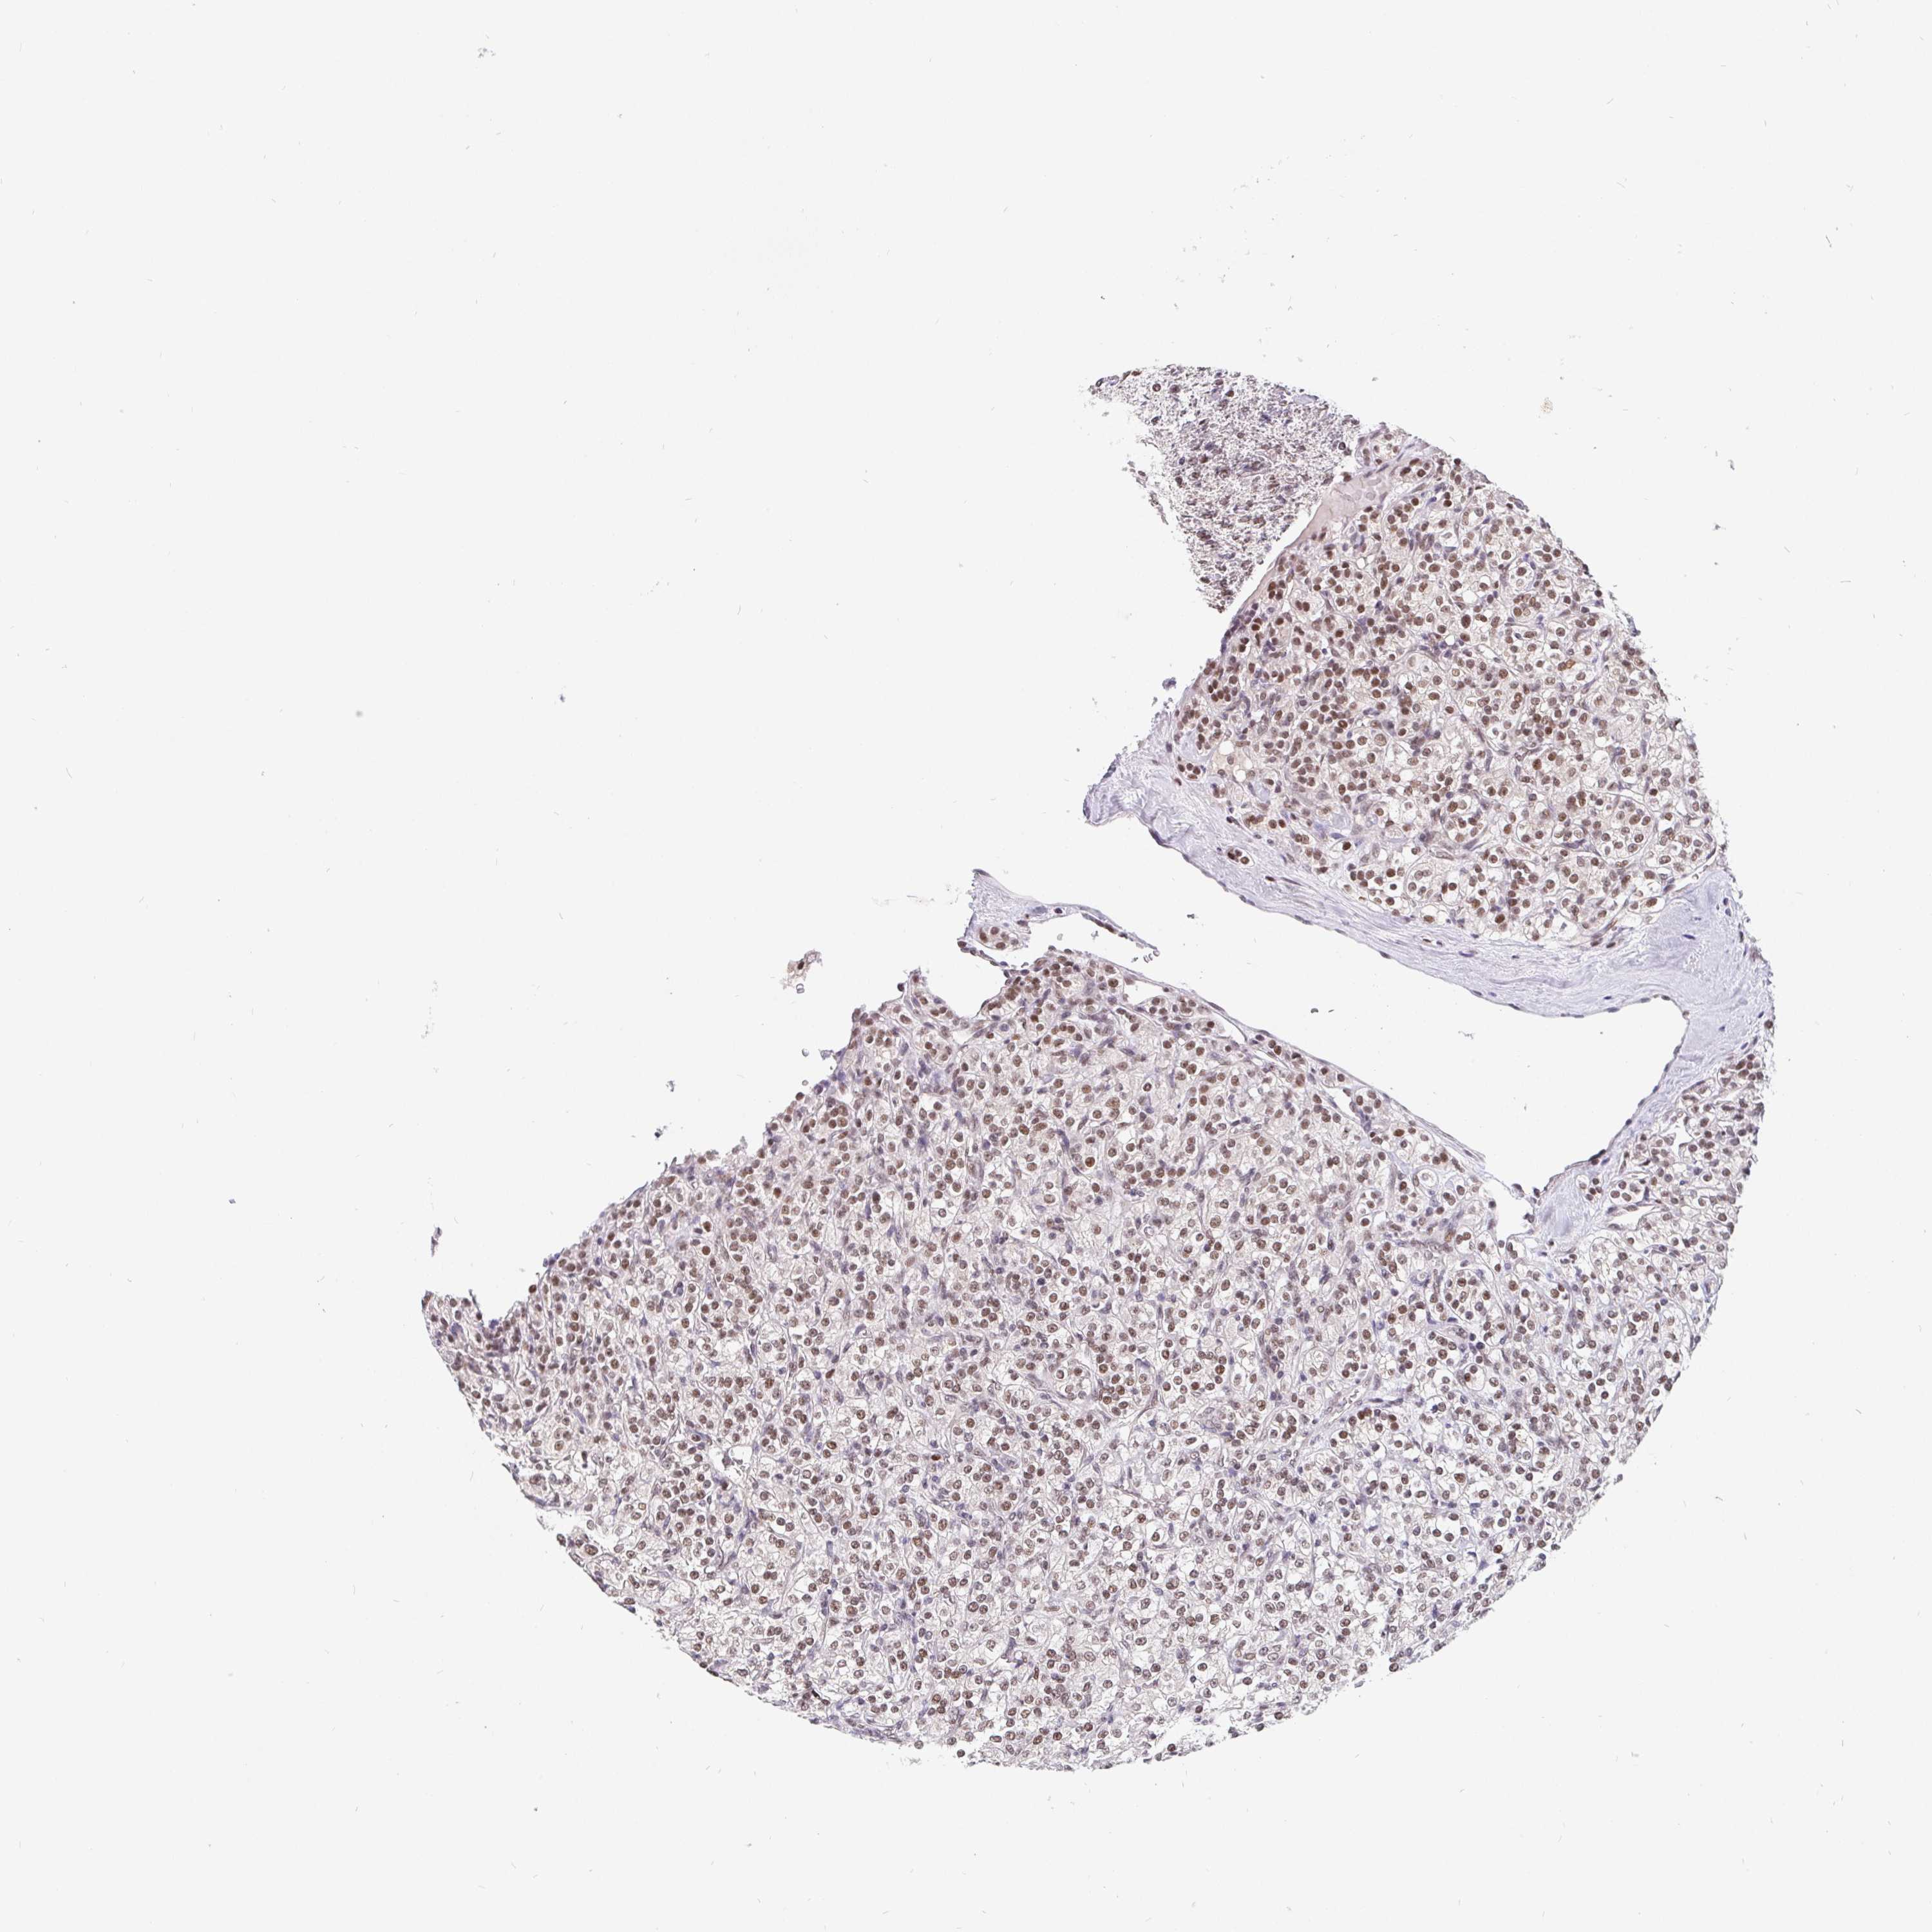

KIDNEY RENAL CLEAR CELL CARCINOMA (TCGA) - Interactive survival scatter ploti

The Survival Scatter plot shows the clinical status (i.e. dead or alive) for all individuals in the patient cohort, based on the same data that underlies the corresponding Kaplan-Meier plots. Patients that are alive at last time for follow-up are shown in blue and patients who have died during the study are shown in red.

The x-axis shows the expression levels (FPKM) of the investigated gene in the tumor tissue at the time of diagnosis. The y-axis shows the follow-up time after diagnosis (years). Both axes are complimented with kernel density curves demonstrating the data density over the axes. The top density plot shows the expression levels (FPKM) distribution among dead (red) and alive patients (blue). The right density plot shows the data density of the survived years of dead patients with high and low expression levels respectively, stratified using the cutoff indicated by the vertical dashed line through the Survival Scatter plot. This cutoff is automatically defined based on the FPKM cutoff that minimizes the p-score. The cutoff can be changed by dragging the vertical line or by entering a cutoff value in the square labeled "Current cut-off".

Under the Survival Scatter plot the p-score landscape (black curve; left axis) is shown together with dead median separation (red curve; right axis). Dead median separation is the difference in median mRNA expression between patients who have died with high and low expression, respectively. It is calculated as follows: median FPKM expression of dead patients with high expression - median FPKM expression of dead patients with low expression. This is intended to aid the user in visually exploring custom cutoffs and the associated p-scores and dead median separation.

Individual patient data is displayed and can be filtered by clicking on one or more of the category buttons on the top of the page. Categories describing expression level and patient information include: high, low, alive, dead, female, male and tumor stages. The scale of the x-axis can be toggled between linear and log-scale by clicking on the "x log" button. Mouse-over function shows TCGA ID, patient information and mRNA expression (FPKM) for each patient.

& Survival analysisi

Kaplan-Meier plots summarize results from analysis of correlation between mRNA expression level and patient survival. Patients were divided based on level of expression into one of the two groups "low" (under cut off) or "high" (over cut off). X-axis shows time for survival (years) and y-axis shows the probability of survival, where 1.0 corresponds to 100 percent.

POU2F1 is not prognostic in Kidney Renal Clear Cell Carcinoma (TCGA)

: 3.91

Average pTPM 3.0

Number of samples 521